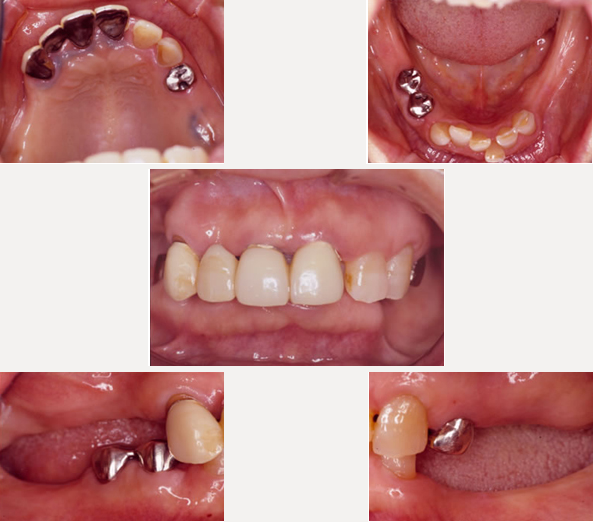

治療前

上下の奥歯がないまま10数年たっていました。前歯に負担がかかりついには上の前歯が脱落してしまいました。前歯だけを治療してもまた壊れてしまいます。奥歯をしっかり咬めるようにすることが大事です。